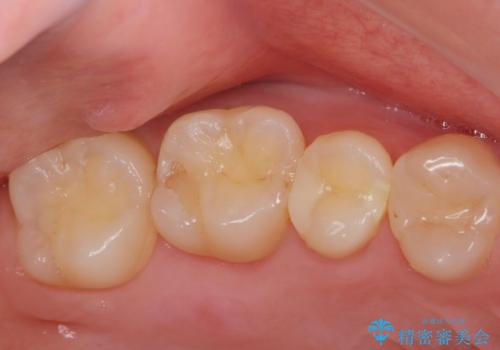

虫歯の再発リスクが高い樹脂修復部分をe-maxインレーに

- 歯と歯の間に古い樹脂の治療がされていて虫歯の再発のリスクが高まるためにe-maxインレー(セラミック)治療を行いました。

適合の良い詰め物が入りました。

セラミックは適合がよく虫歯の再発のリスクが低くなります。